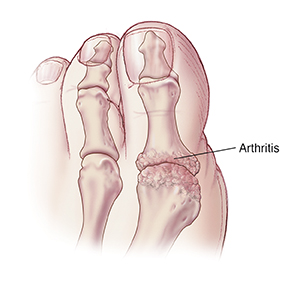

Degenerative joint disease (arthritis) often happens in the joint of the big toe. In addition, bone growth may cause pain and stiffness in the joint. Left untreated, arthritis can break down the cartilage and destroy the joint. Your treatment choices depend on how damaged your joint is. There are several nonsurgical treatments. But if these are not helpful, surgery may be considered.

Cheilectomy

This is done when the arthritic joint and cartilage can be saved. A bone spur caused by arthritis may be on the top of the big toe joint. The procedure involves removing this bone spur, often with a small part of the top of the joint itself. You will need to wear a surgical shoe for a few weeks. Once the foot heals, joint movement can be restored.